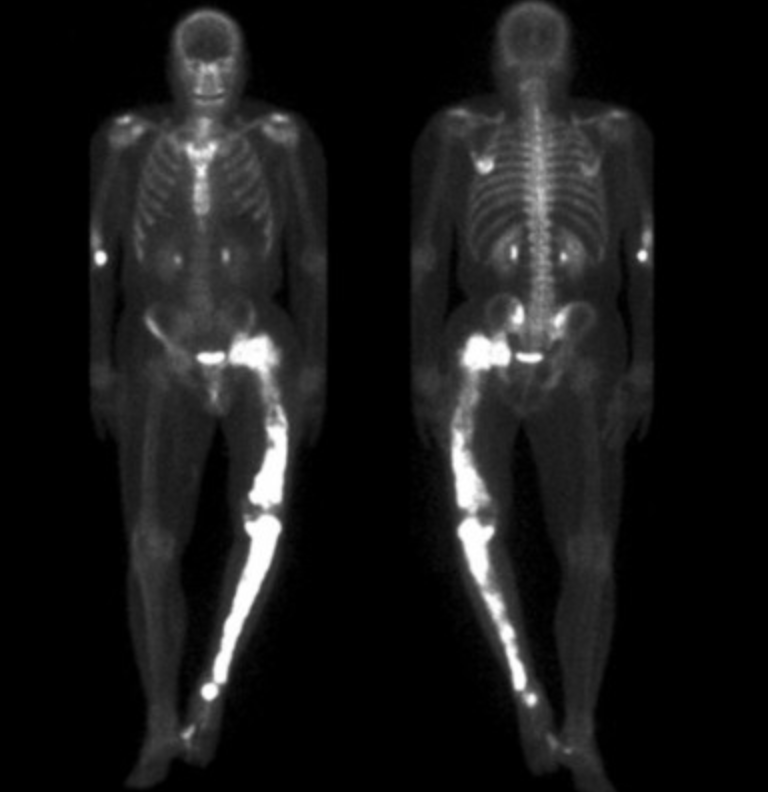

Hypertrophic Osteoathropathy

• Look at shins and you will see linear areas of high uptake along periosteum

• Called tram tracking

• Next step - likely CT chest for lung cancer eval

• Other DDx:

• Hypoxia, cyanotic heart disease, pulmonary pathology